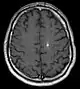

Developmental venous abnormality seen on a (T1 axial contrast enhanced) MRI.

In up to 30% there is a coincidence of CCM with a venous angioma, also known as a developmental venous anomaly. These lesions appear either as enhancing linear blood vessels or caput medusae, a radial orientation of small vessels that resemble the hair of Medusa from Greek mythology. These lesions are thought to represent developmental anomalies of normal venous drainage. These lesions should not be removed, as venous infarcts have been reported. When found in association with a CCM that needs resection, great care should be taken not to disrupt the angioma.